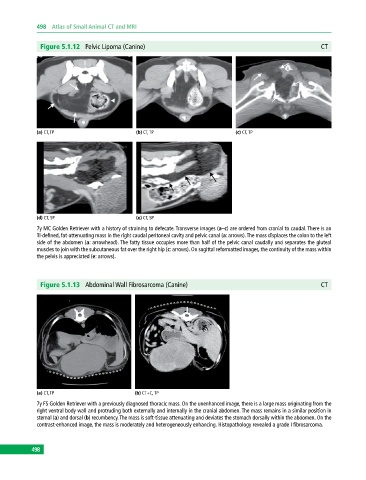

Figure 5.1.12 Pelvic Lipoma (Canine) CT

(a) CT, TP (b) CT, TP (c) CT, TP

(d) CT, SP (e) CT, SP

7y MC Golden Retriever with a history of straining to defecate. Transverse images (a–c) are ordered from cranial to caudal. There is an

ill‐defined, fat‐attenuating mass in the right caudal peritoneal cavity and pelvic canal (a: arrows). The mass displaces the colon to the left

side of the abdomen (a: arrowhead). The fatty tissue occupies more than half of the pelvic canal caudally and separates the gluteal

muscles to join with the subcutaneous fat over the right hip (c: arrows). On sagittal reformatted images, the continuity of the mass within

the pelvis is appreciated (e: arrows).

Figure 5.1.13 Abdominal Wall Fibrosarcoma (Canine) CT

(a) CT, TP (b) CT+C, TP

7y FS Golden Retriever with a previously diagnosed thoracic mass. On the unenhanced image, there is a large mass originating from the

right ventral body wall and protruding both externally and internally in the cranial abdomen. The mass remains in a similar position in

sternal (a) and dorsal (b) recumbency. The mass is soft‐tissue attenuating and deviates the stomach dorsally within the abdomen. On the

contrast‐enhanced image, the mass is moderately and heterogeneously enhancing. Histopathology revealed a grade I fibrosarcoma.